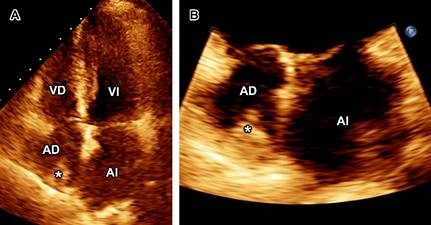

A la exploración física, ruidos cardiacos y respiratorios se auscultaron sin alteraciones. Laboratorios solo reportaron anemia (hemoglobina 8.7 g/dL). Ante sospecha de EI se tomaron hemocultivos y se inició tratamiento con vancomicina más ceftazidima. El ecocardiograma transtorácico (ECOTT) con mala ventana acústica mostró catéter de hemodiálisis engrosado con vegetación en la aurícula derecha (Figura 1), y se realizó ecocardiograma transesofágico (ECOTE), observándose vegetación en el catéter de hemodiálisis así como en aurícula derecha y sin compromiso valvular (Figura 2).

Figura 1: Ecocardiograma transtorácico: vista apical cuatro cámaras (A) con acercamiento a aurículas (B) que muestra catéter de hemodiálisis engrosado con vegetación (*) en aurícula derecha.